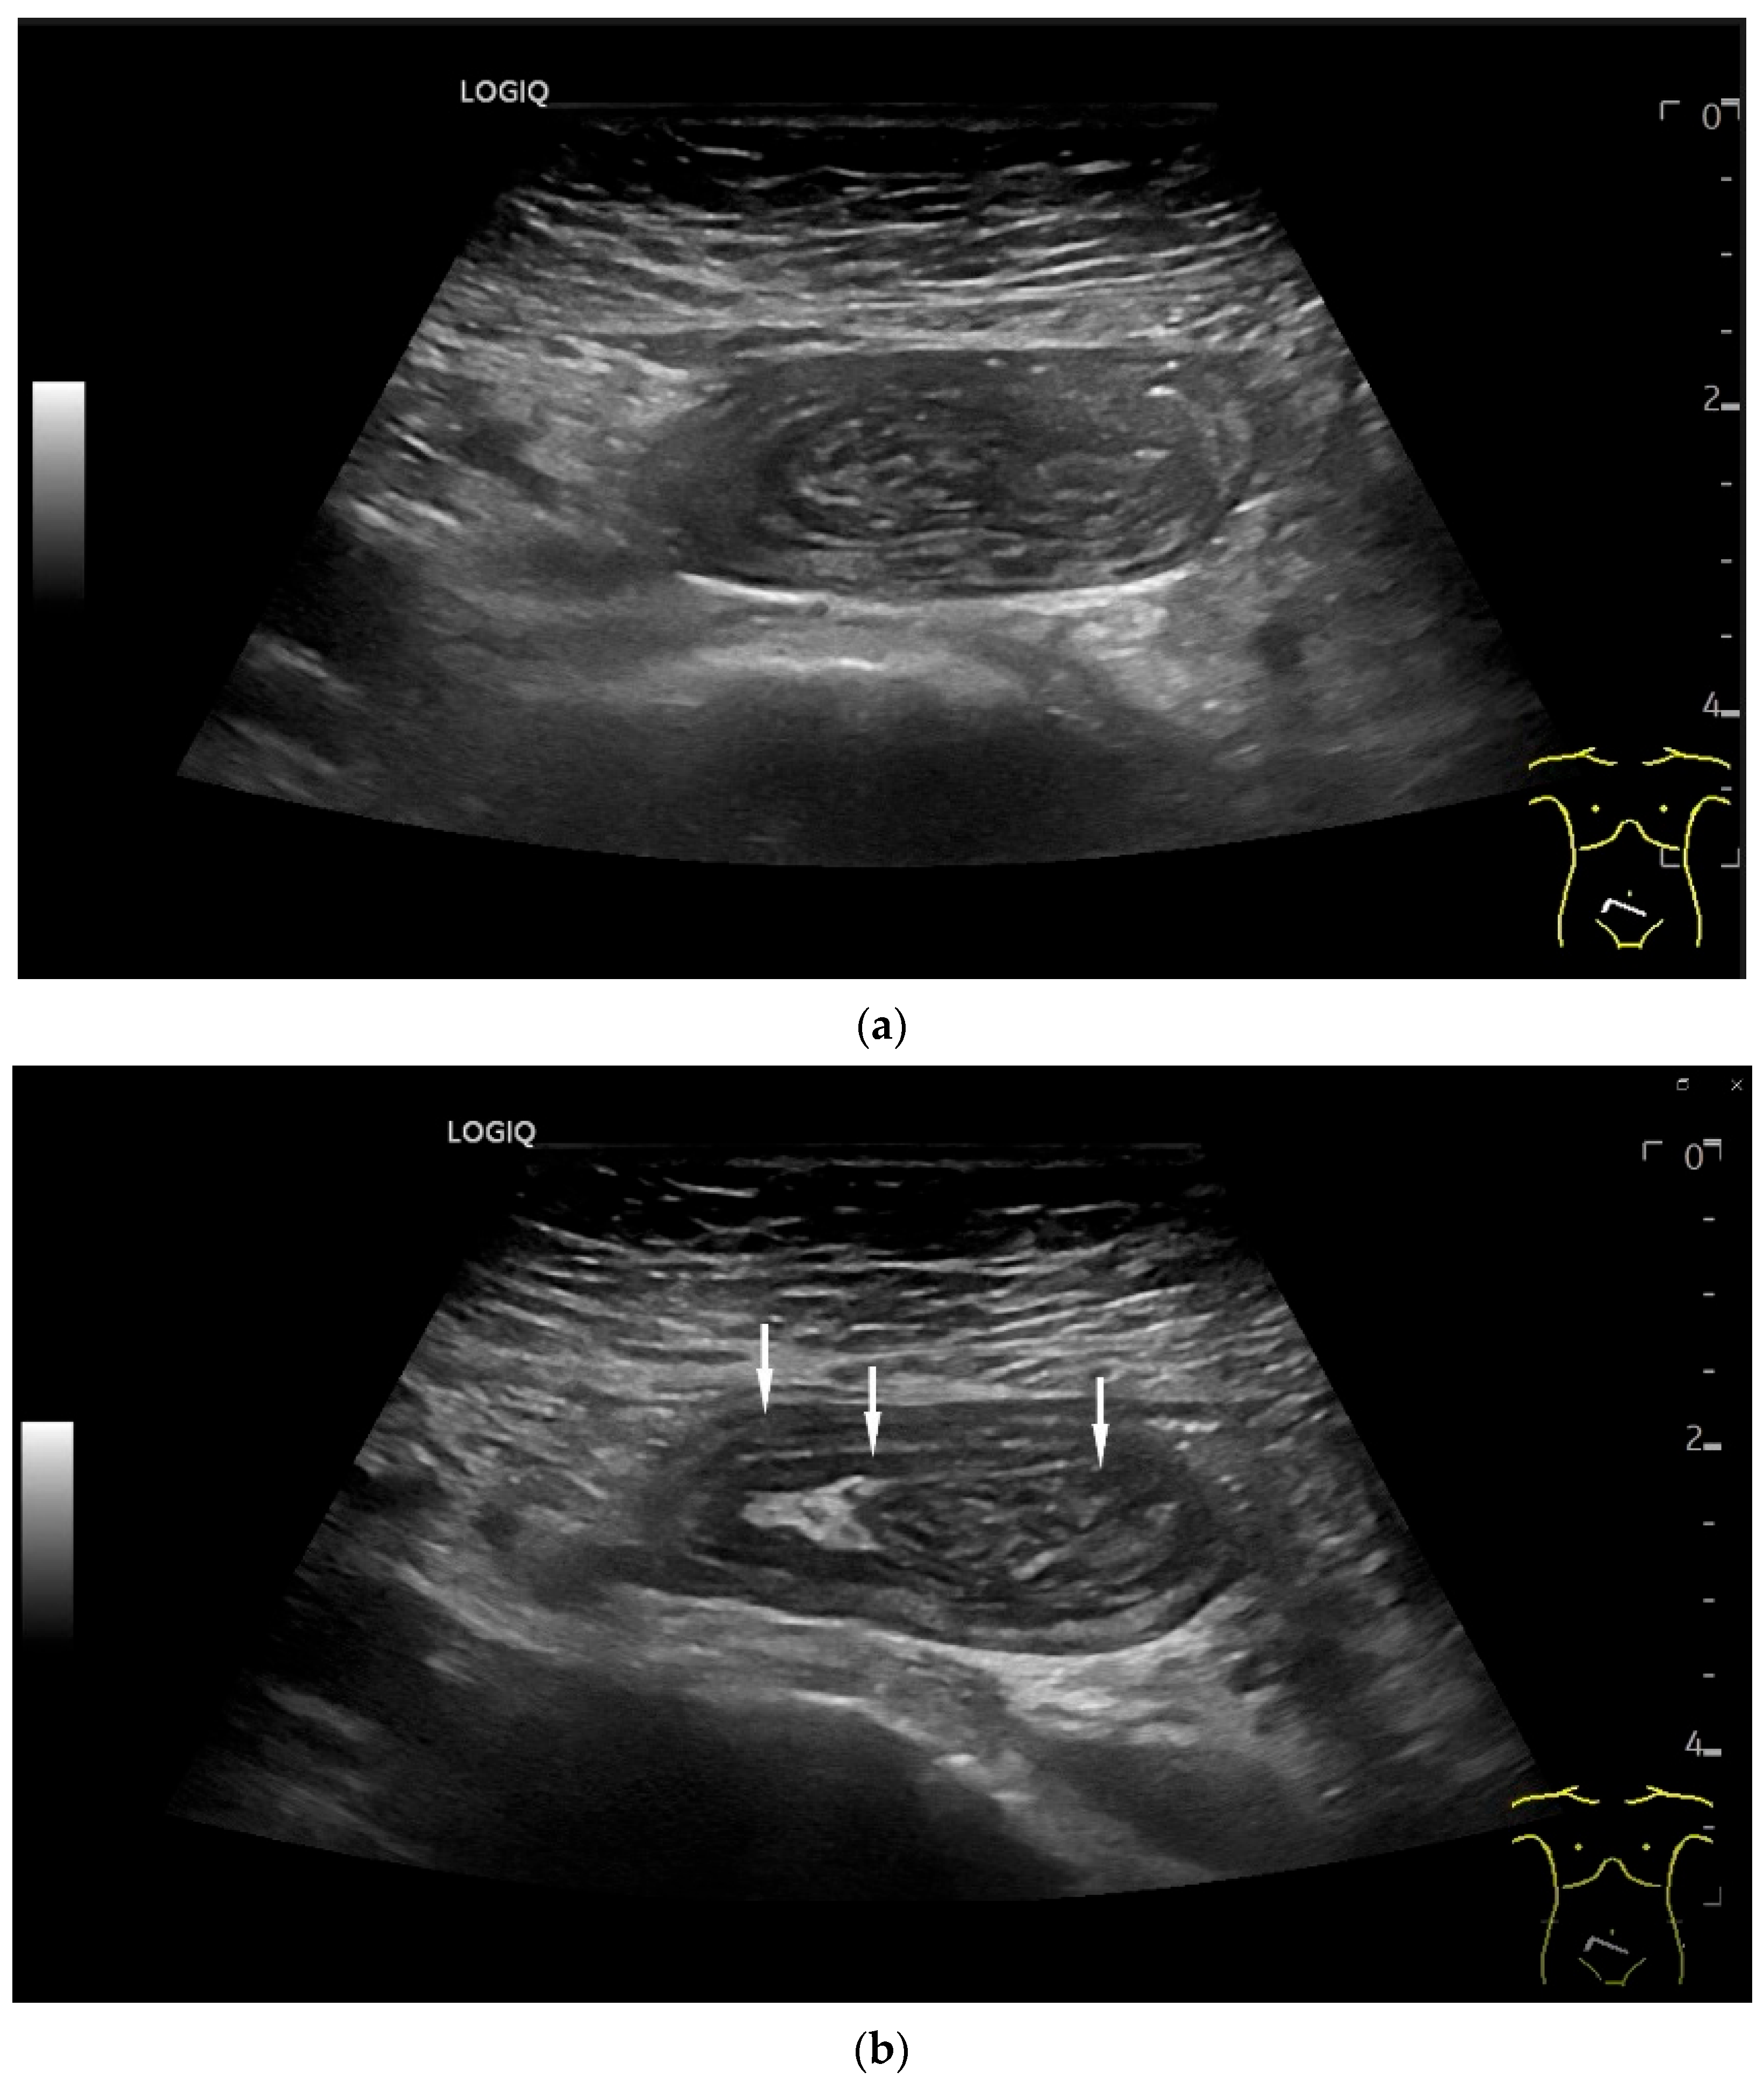

- Hasegawa, T.; Sumimura, J.; Mizutani, S.; Tazuke, Y.; Okuda, S.; Dezawa, T. The doughnut sign: An ultrasound finding in pediatric intestinal Burkitt’s lymphoma. Pediatr. Surg. Int. 1998, 13, 297–298. [Google Scholar] [CrossRef] [PubMed]

- Hasaballah, M.; Abdel-Malek, R.; Zakaria, Z.; Marie, M.S.; Naguib, M.S. Transabdominal ultrasonographic features in the diagnosis of gastrointestinal lymphoma. J. Gastrointest. Oncol. 2018, 9, 1190–1197. [Google Scholar] [CrossRef]

- Goerg, C.; Schwerk, W.B.; Goerg, K. Gastrointestinal lymphoma: Sonographic findings in 54 patients. Am. J. Roentgenol. 1990, 155, 795–798. [Google Scholar] [CrossRef]

| Lymphoma | Very pronounced wall thickening with marked hypoechogenicity. Large regional and distant lymph nodes. Look for splenic infiltration. Tumor vessels on CDI and hyperenhancement on CEUS. Heterogeneous hyperechogenicity of the mesentery with walling of the mesenteric vessels. Multiple localizations are possible. |

| Intussusception | The small intestine proximal to the tumor is invaginated. More than five wall layers are seen in an onion-skin shape. |